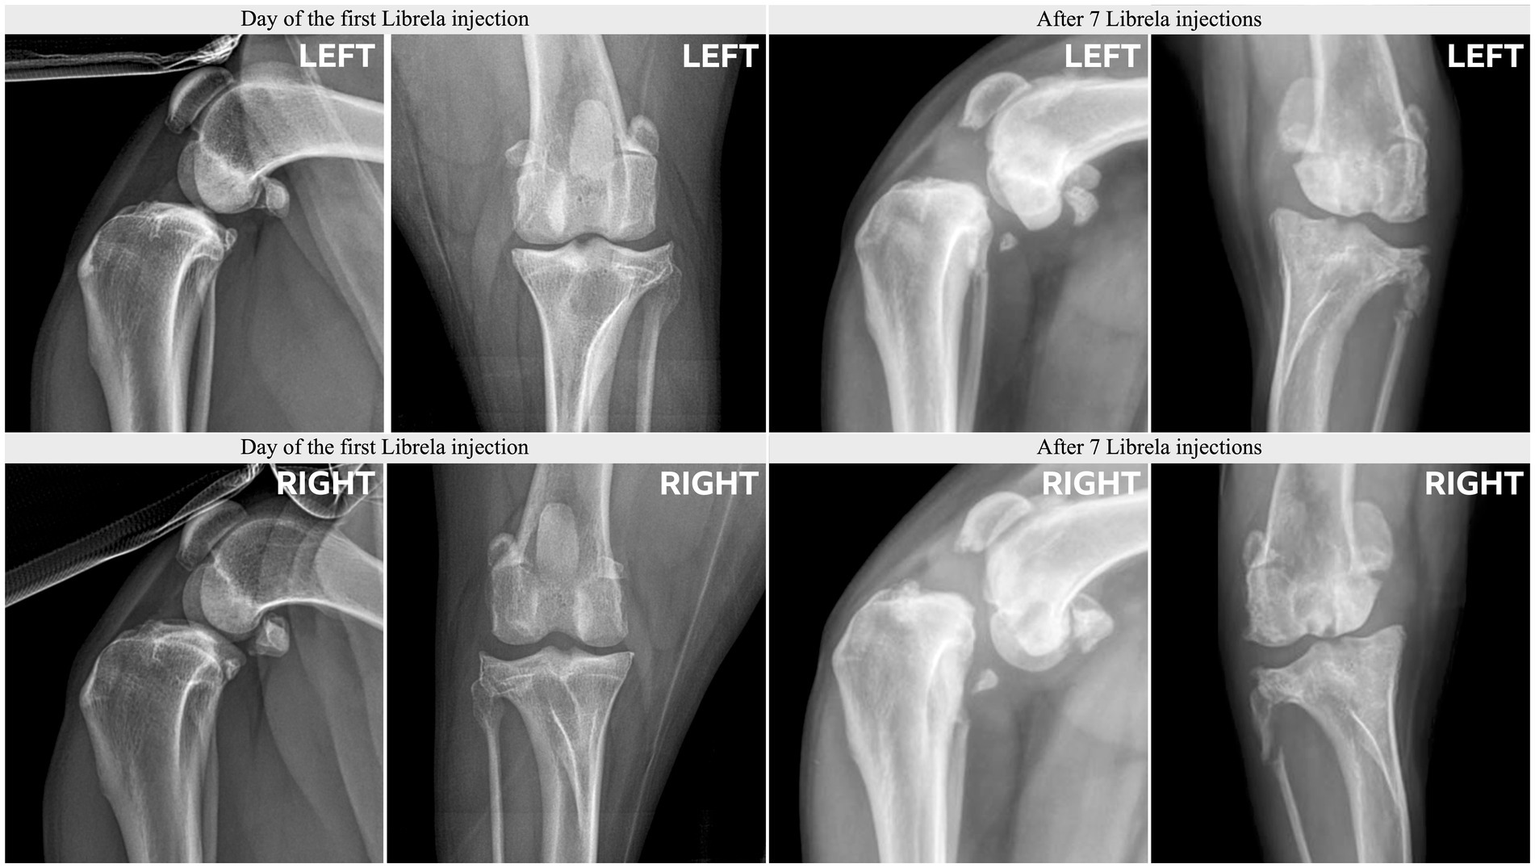

3.3 Case series adjudication outcome

Clinical and radiographic characteristics are summarized in Table 2 and Figures 5–13. Mean ± SD number of Librela doses was 12.7 ± 9.5 (range 1–30), with a dose range of 0.4–0.76 mg/kg (mean 0.62 ± 0.08 mg/kg). Referral for investigation of suspected RPOA was made at least 6 months after Librela initiation in 13/19 cases. Eleven dogs (58%) received regular concurrent NSAIDs. The most frequently affected joint was the elbow (13/19 dogs, 68%), followed by the stifle and hock (two dogs each), and hip (one dog). Seven dogs (37%) sustained pathological fractures, and two (10.5%) had joint luxations. Two dogs with clinically normal hock joints before initiating Librela therapy developed severe non-index hock joint destruction after Librela treatment for elbow OA.

Figure 11

Radiographs from Case 17, a 5-year-old Springer Spaniel, before and after 20 Librela injections.

Figure 12

Case 18, a 5.5-year-old Australian Shepherd, had stable stifle joints before starting Librela. AER: The attending specialist filed a report for suspected RPOA to the MAH, who submitted an AER for ligament ruptures, fractures, and joint subluxation/luxations. Their report designated this reaction as not serious (Supplementary Figure S9).